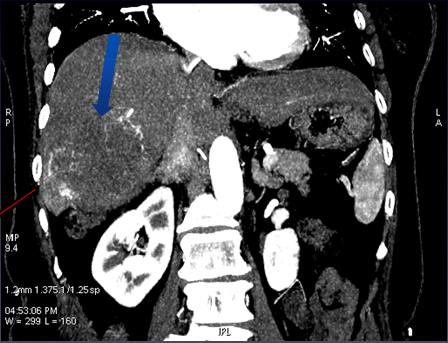

4、血管重建,使用49keV图像观察,显示左右叶病灶丰富的血供情况

图中红、蓝箭头显示肝左右叶病灶分别来源于肝左右动脉